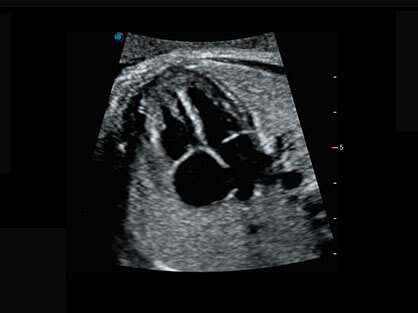

作为P系列家族成员之一,P40 Plus采用新葡的京集团8814检测站高端超声系统平台——极光,并以时尚秀丽、小巧灵动的外观设计绽放出灵动之韵、科技之美。高端平台的使用保证了P40 Plus优质的基础图像;完备的高级功能可满足您全身应用的基本需求;丰富的探头配置、多样的高级4D成像及分析软件为您日益增多的妇产应用需求提供丰富的诊疗方案。

结合新葡的京集团8814检测站超宽频带探头技术优势,能够更好地获得高分辨力与高穿透力的平衡,保证图像质量,为临床诊断保驾护航。

微米成像技术提升了对组织斑点噪声信号的抑制能力,并进一步强化边界信息,从而获得清晰图像。